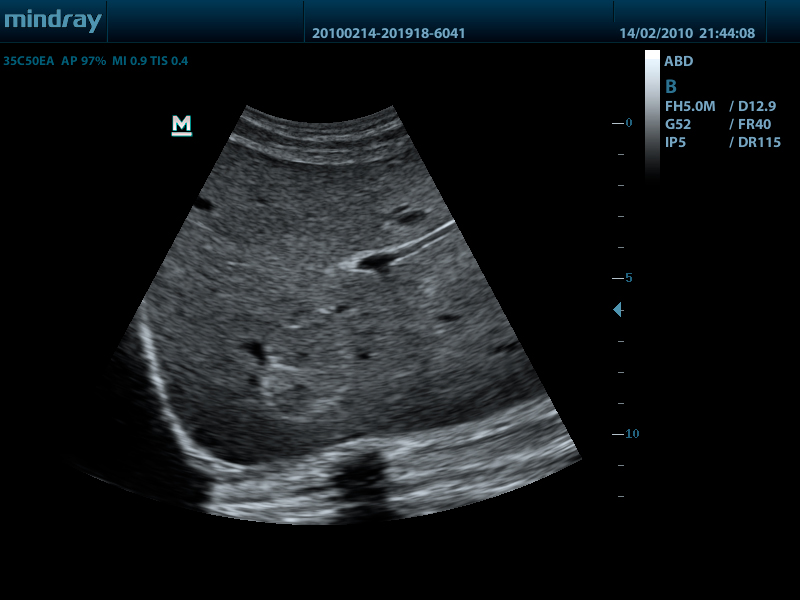

- Конвексный датчик 35C50EA, 1.7 - 6.0 МГц, радиус кривизны 50 мм